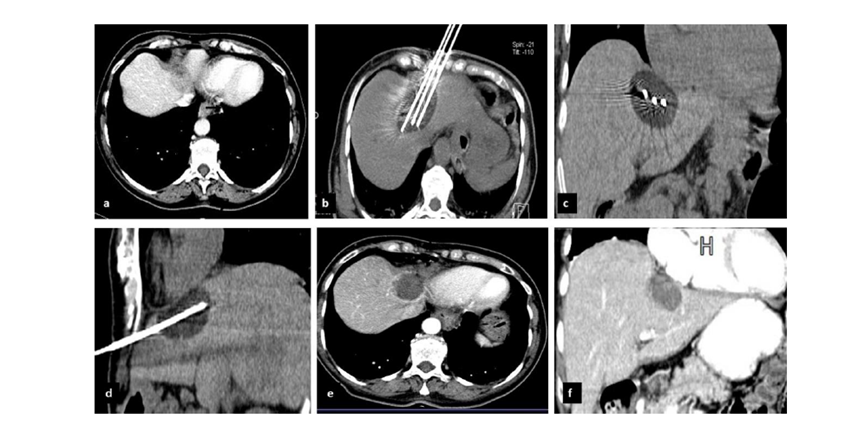

CT引导下冷冻消融

62岁女性,肝转移(卵巢癌)肿瘤的完全消融病例

(a)轴向CT显示病变位置毗邻心脏和上腔静脉(黑色箭头)。

(b)术中轴向CT扫描:使用三个冷冻探针。

(c)冠状面和(d)矢状面显示冰球毗邻心包。

1个月后的轴向(e)和冠状位(f)增强CT扫描显示低密度区域,由于肉芽组织反应引起的边缘增强。